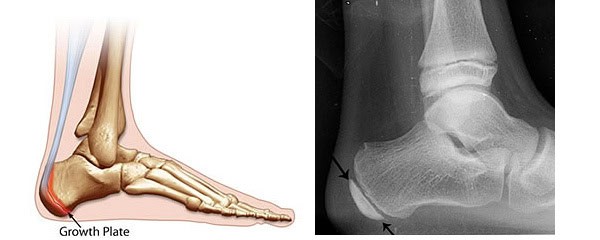

Unlike an adult heel bone the heel bone in a child is in two parts connect by a cartilage growth plate (see picture below).

Xray of a Child's Foot